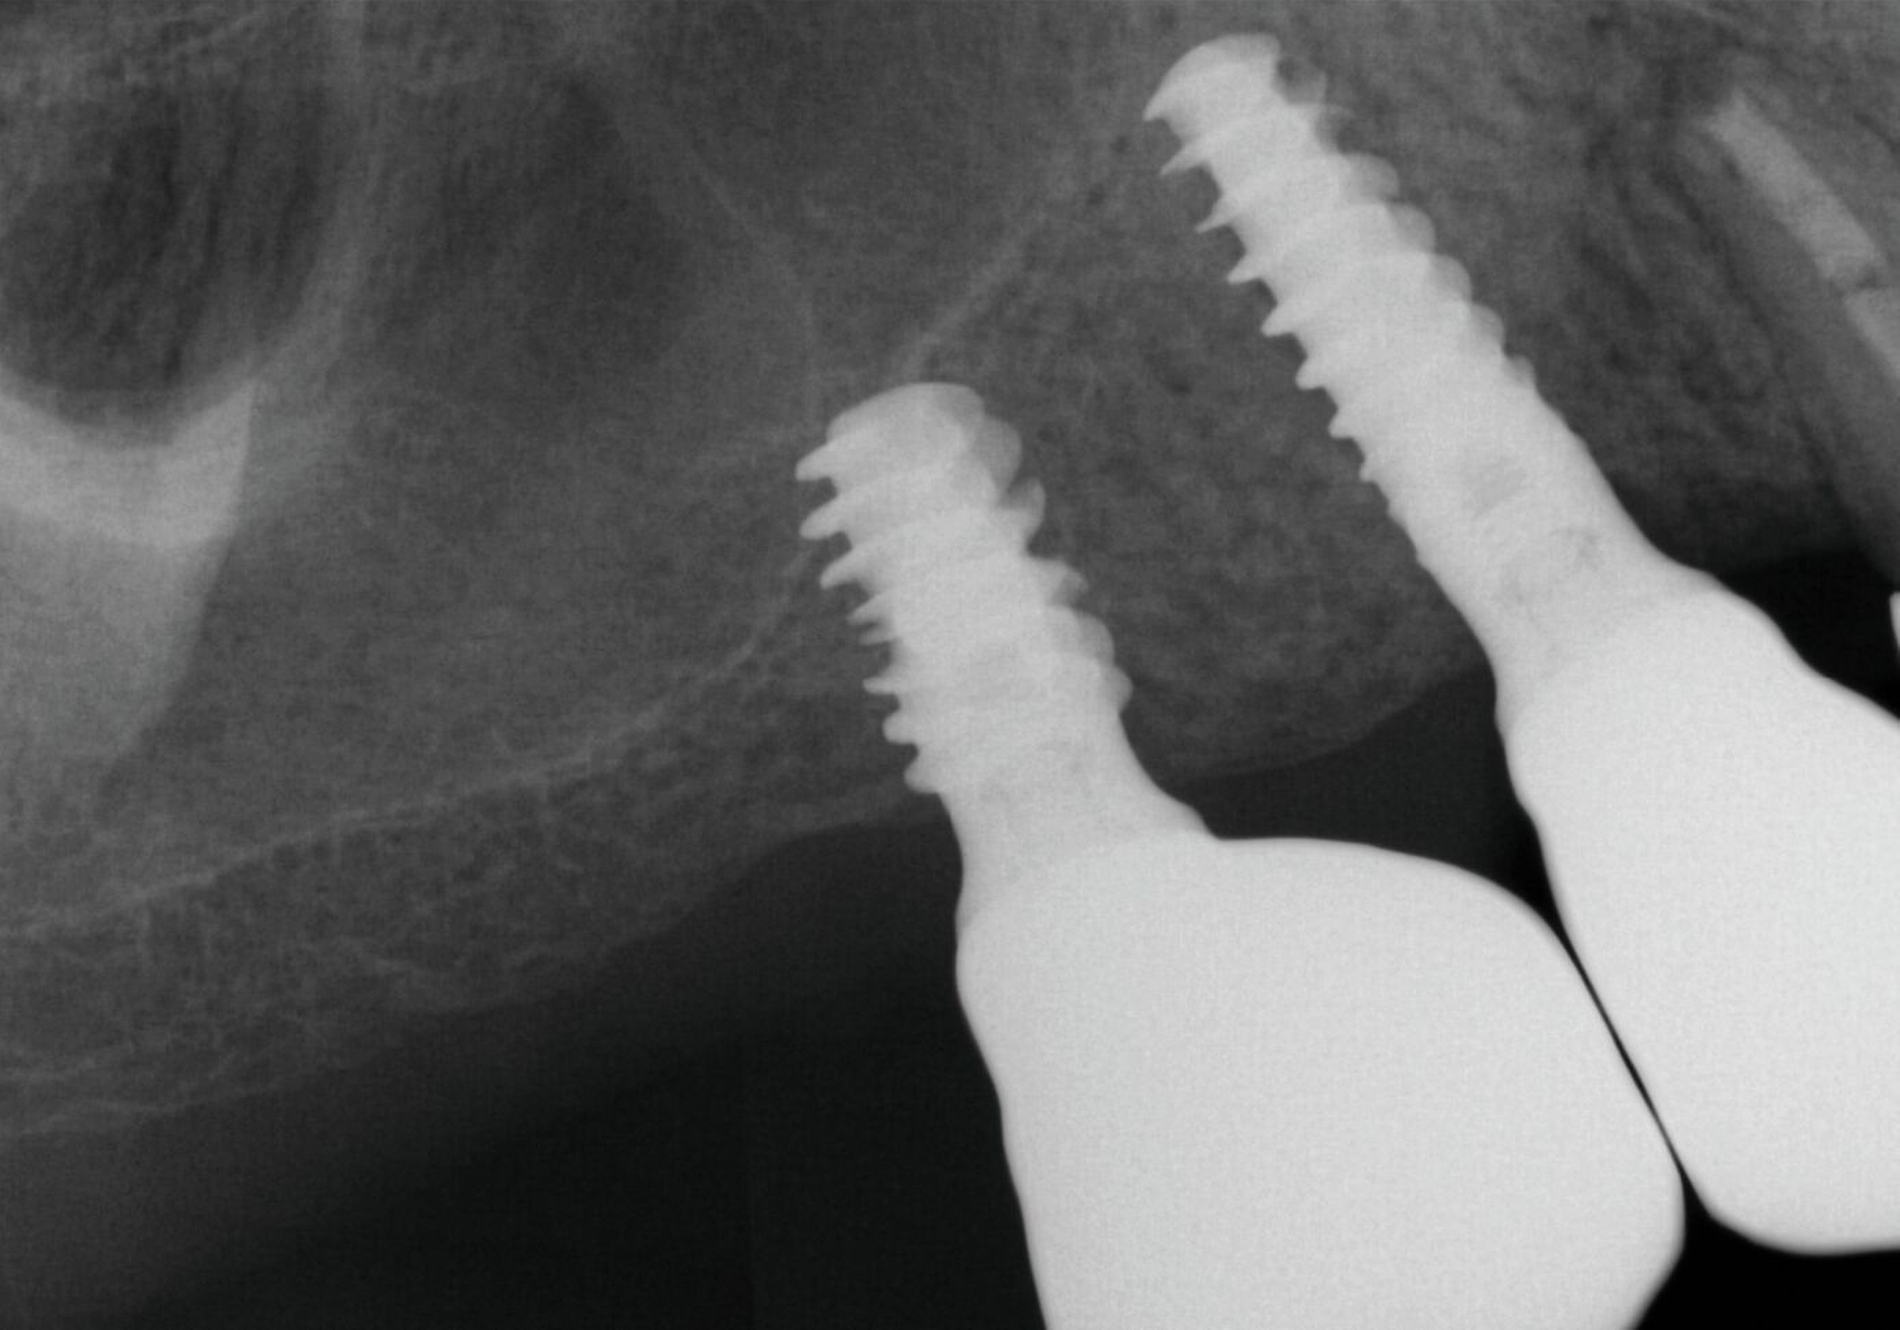

Nach Durchführung einer dentalen Volumentomografie (DVT) wurden daher zahnärztliche Implantate in Regio 14, 15 und 25 im Sinne einer verkürzten Zahnreihe geplant und inseriert (Abbildung 7). Nach dreimonatiger subgingivaler, konventioneller Einheilzeit wurden die Implantate freigelegt. Zwei Wochen später begann man die vorhandenen Primärkronen zu entfernen. Die Stümpfe wurden nachpräpariert und es wurden erneut Fäden gelegt (Abbildung 8a und 8b).

Um den Sitz der Implantatkronen nach dem Einsetzen zu prüfen, wurden intraorale Tubusaufnahmen im Sinne eines Baseline-Röntgens angefertigt (Abbildung 9). In den Folgeterminen wurde dem Patienten noch eine Aufbissschiene für den Oberkiefer eingegliedert, um etwaigem nächtlichen Bruxismus vorzubeugen. Für die Nachsorge empfiehlt sich ein halbjährliches Kontrollintervall.